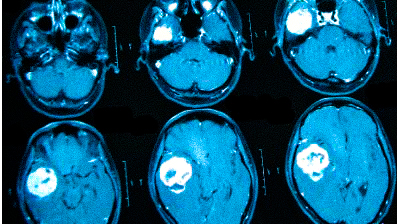

Онкологи считают, что при нарастающих головных болях с прочими необъяснимыми симптомами (обмороками, ухудшением памяти, выпадением полей зрения, давлением на глазные яблоки и др.) в первую очередь следует исключить опухолевую патологию

Частые головные боли вызывают разные причины. Иногда так проявляется серьезное заболевание. В 90% случаев после определения генеза возможно адекватное лечение, которое улучшит качество жизни. Состояния, для которых типична цефалгия::

опухоли;

-

сосудистые заболевания.